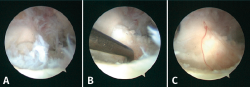

Figura 5. Imágenes artroscópicas de lesiones osteocondrales. A: localización en la zona 6 antes del tratamiento; B: después del desbridamiento del cartílago dañado hasta el borde estable y el curetaje del hueso subcondral necrótico; C: tras la microfractura y la liberación del torniquete de isquemia, que permite apreciar el sangrado conseguido con la estimulación de la lesión.

En relación con el tratamiento quirúrgico, la literatura actual sugiere que se utilicen las técnicas de reparación (estimulación por microfracturas) para el tratamiento de lesiones de hasta 15 mm de diámetro o 1,5 cm2, estando indicadas estrategias de sustitución o injerto para lesiones más grandes y/o quísticas (Figura 5)(29,47). En la Figura 6 se muestra un algoritmo de tratamiento para el manejo de estas LOC.